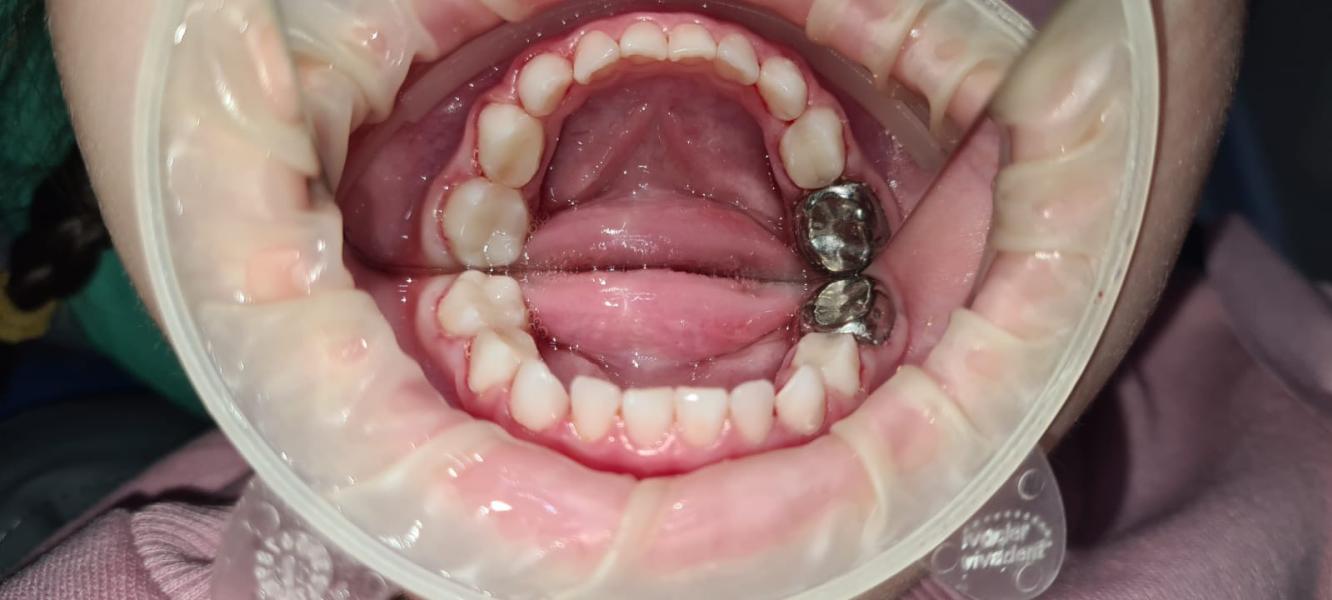

Еще поставили одну коронку

Под наркозом 4 часа 15 минут, после наркоза проснулась через 30 минут. Не плакали, не капризничали хата, домой пришли сидим кушаем🥰